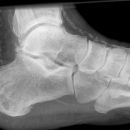

Entenschnabelfraktur